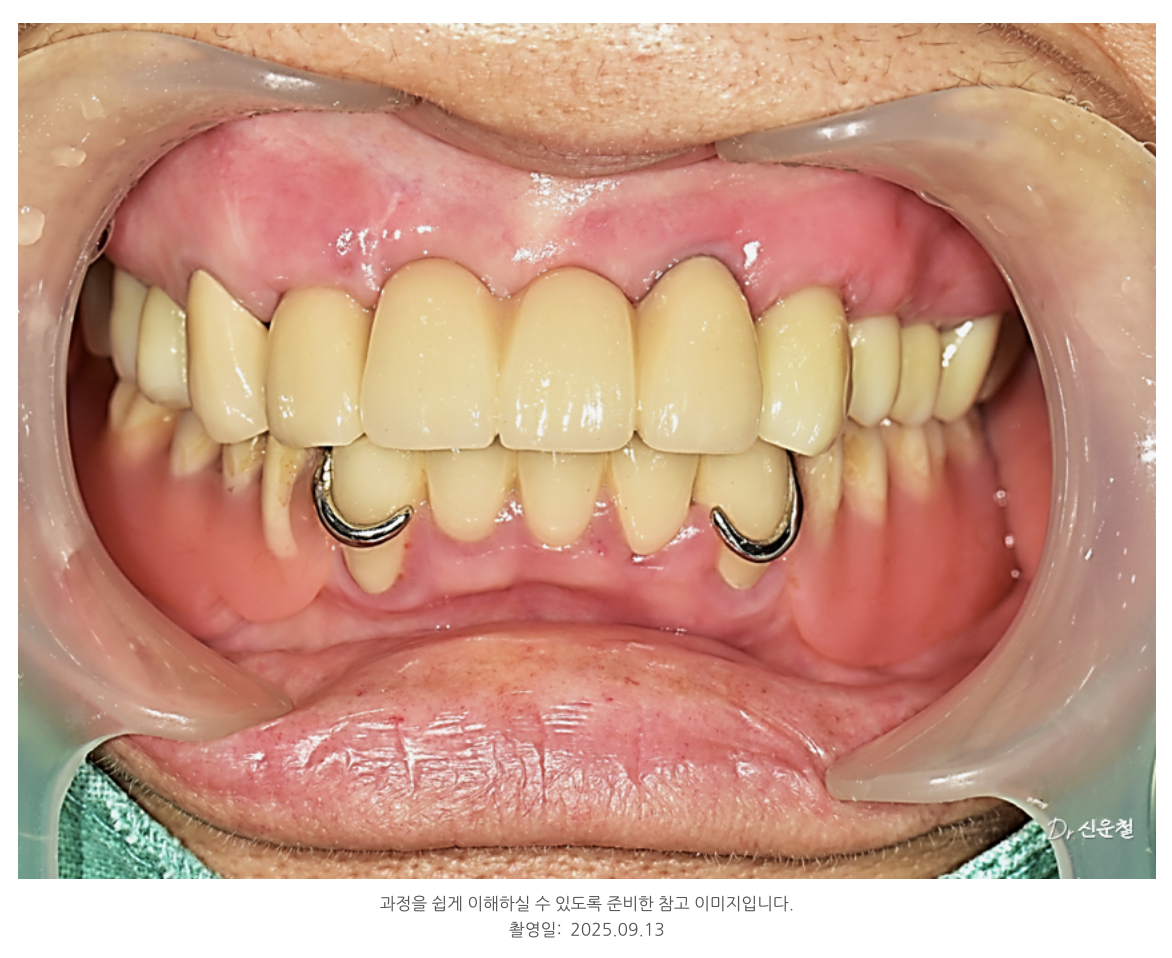

식사, 발음, 외적인 만족도 모두 개선되었습니다.

???? 치료 결과

수개월의 치료 끝에, 환자분께서 거울을 보며 하신 말씀입니다.

“이제는 정말, 나도 사람 같네요.”

식사도, 웃음도, 자신감도 되찾으셨고

“멀리서 왔지만 여기서 치료받길 잘했다”고 웃으셨습니다.